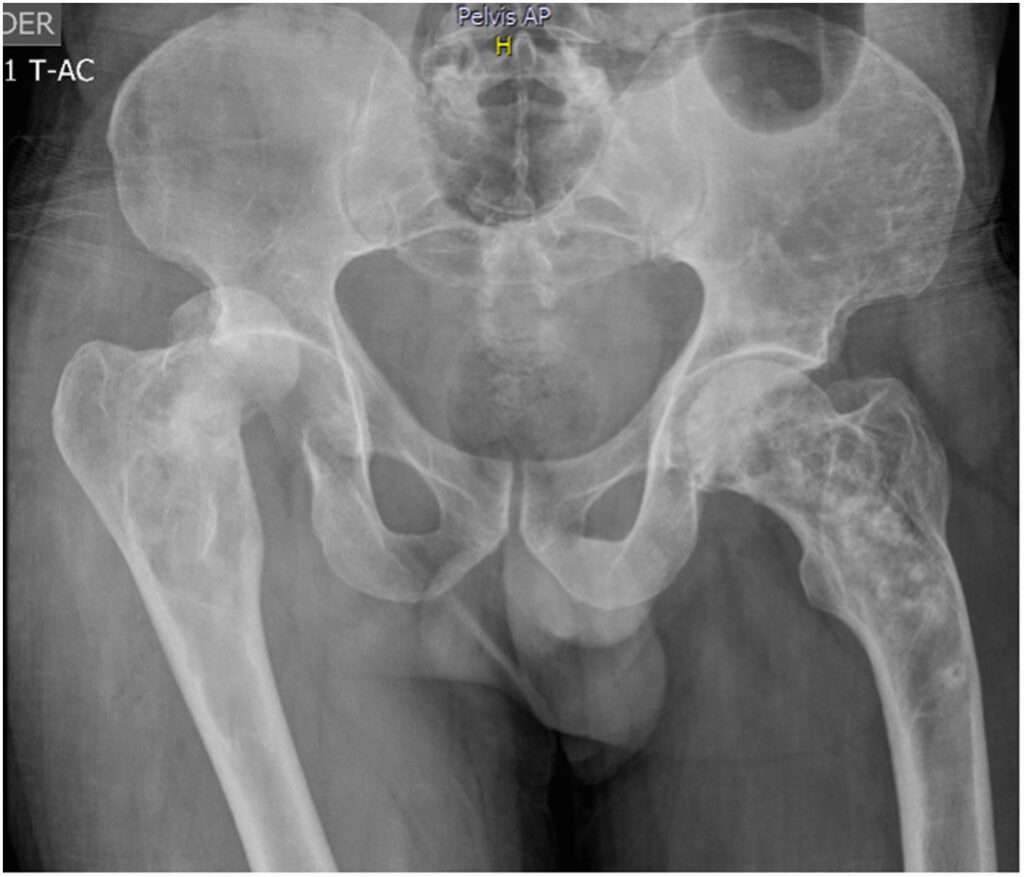

La enfermedad de Paget del hueso se caracteriza por su curso clínico generalmente leve y asintomático en aproximadamente el 75% de los casos, lo que significa que muchos pacientes pueden no experimentar síntomas evidentes durante las primeras etapas de la enfermedad. A pesar de la naturaleza silente de la enfermedad en muchas personas, cuando se presenta, puede afectar varios huesos en el 72% de los casos, lo que se conoce como forma poliostótica, mientras que en el 28% de los casos solo se ve afectado un hueso, lo que se denomina forma monoestótica. Las localizaciones más comunes de afectación incluyen la pelvis, las vértebras, el fémur, el húmero y el cráneo.

En cuanto a la imagenología, las radiografías simples o las tomografías computarizadas (TC) son fundamentales para el diagnóstico de la enfermedad de Paget. Estas pruebas revelan lesiones osteolíticas en los huesos afectados, que aparecen como áreas radiolúcidas (zonas más oscuras en la radiografía) debido a la destrucción ósea. Un hallazgo característico en el cráneo es la presencia de «osteoporosis circunscrita», donde las áreas de destrucción ósea se presentan de forma focalizada. En los huesos largos, se pueden observar lesiones líticas que avanzan de manera similar a las llamas de fuego, lo que ayuda a diferenciar estas lesiones de otras enfermedades óseas. En las vértebras, las lesiones pueden adoptar una forma peculiar, conocida como «trébol» o «corazón», a veces denominada «signo de Mickey Mouse», lo que puede ayudar a distinguirlas de las metástasis óseas, que generalmente tienen una apariencia más uniforme y difusa.

Las lesiones óseas en la enfermedad de Paget pueden pasar por diferentes fases, comenzando con una fase lítica en la que la resorción ósea es predominante, seguida de una fase mixta, en la que coexisten la resorción y la formación ósea desorganizada, y, finalmente, una fase esclerótica en la que predomina la formación ósea excesiva, lo que lleva a que los huesos afectados se engrosen y se deformen. Este proceso progresivo de destrucción y remodelado anómalo es lo que da lugar a las deformidades típicas asociadas con la enfermedad de Paget.